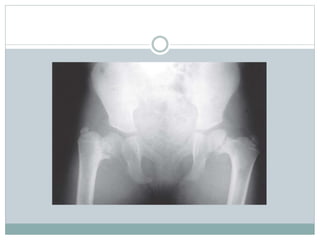

 A full term girl was born via vaginal delivery, her

birth weight was 1800 g,she had anomalous

pulmonary venous drainage and for that reason she

was managed at the intensive care unit until the age

of 12 days and was operated for some cardiac and

pulmonary anomaly, the platelet count was within

normal range (150-400×103/ml), WBC count was

normal (10-20×103/ml) no fever was registered. She

subsequently did well and met all of her early

developmental milestones, including walking at age

12 months.

 She had no orthopedic issues until she was 3 year-10

months-old, when she presented with limp related to

the right lower limb, with no pain. She had a leg-length

discrepancy of 2 cm (right - left), limited right

hip abduction to 25°, and internal rotation to 5°, also

had a positive Trendelenburg test. No